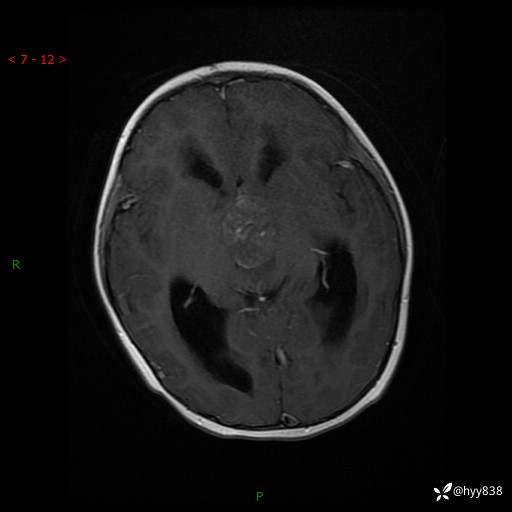

理解“经典”,从经典病例开始,3岁小女孩,行走不稳2个月,加重1个月--结果公布

性别:女

年龄:3岁

简要病史:发现行走不稳2个月,加重1个月

颅脑MRI平扫+增强

三脑室、四脑室多发病变,如何分析?